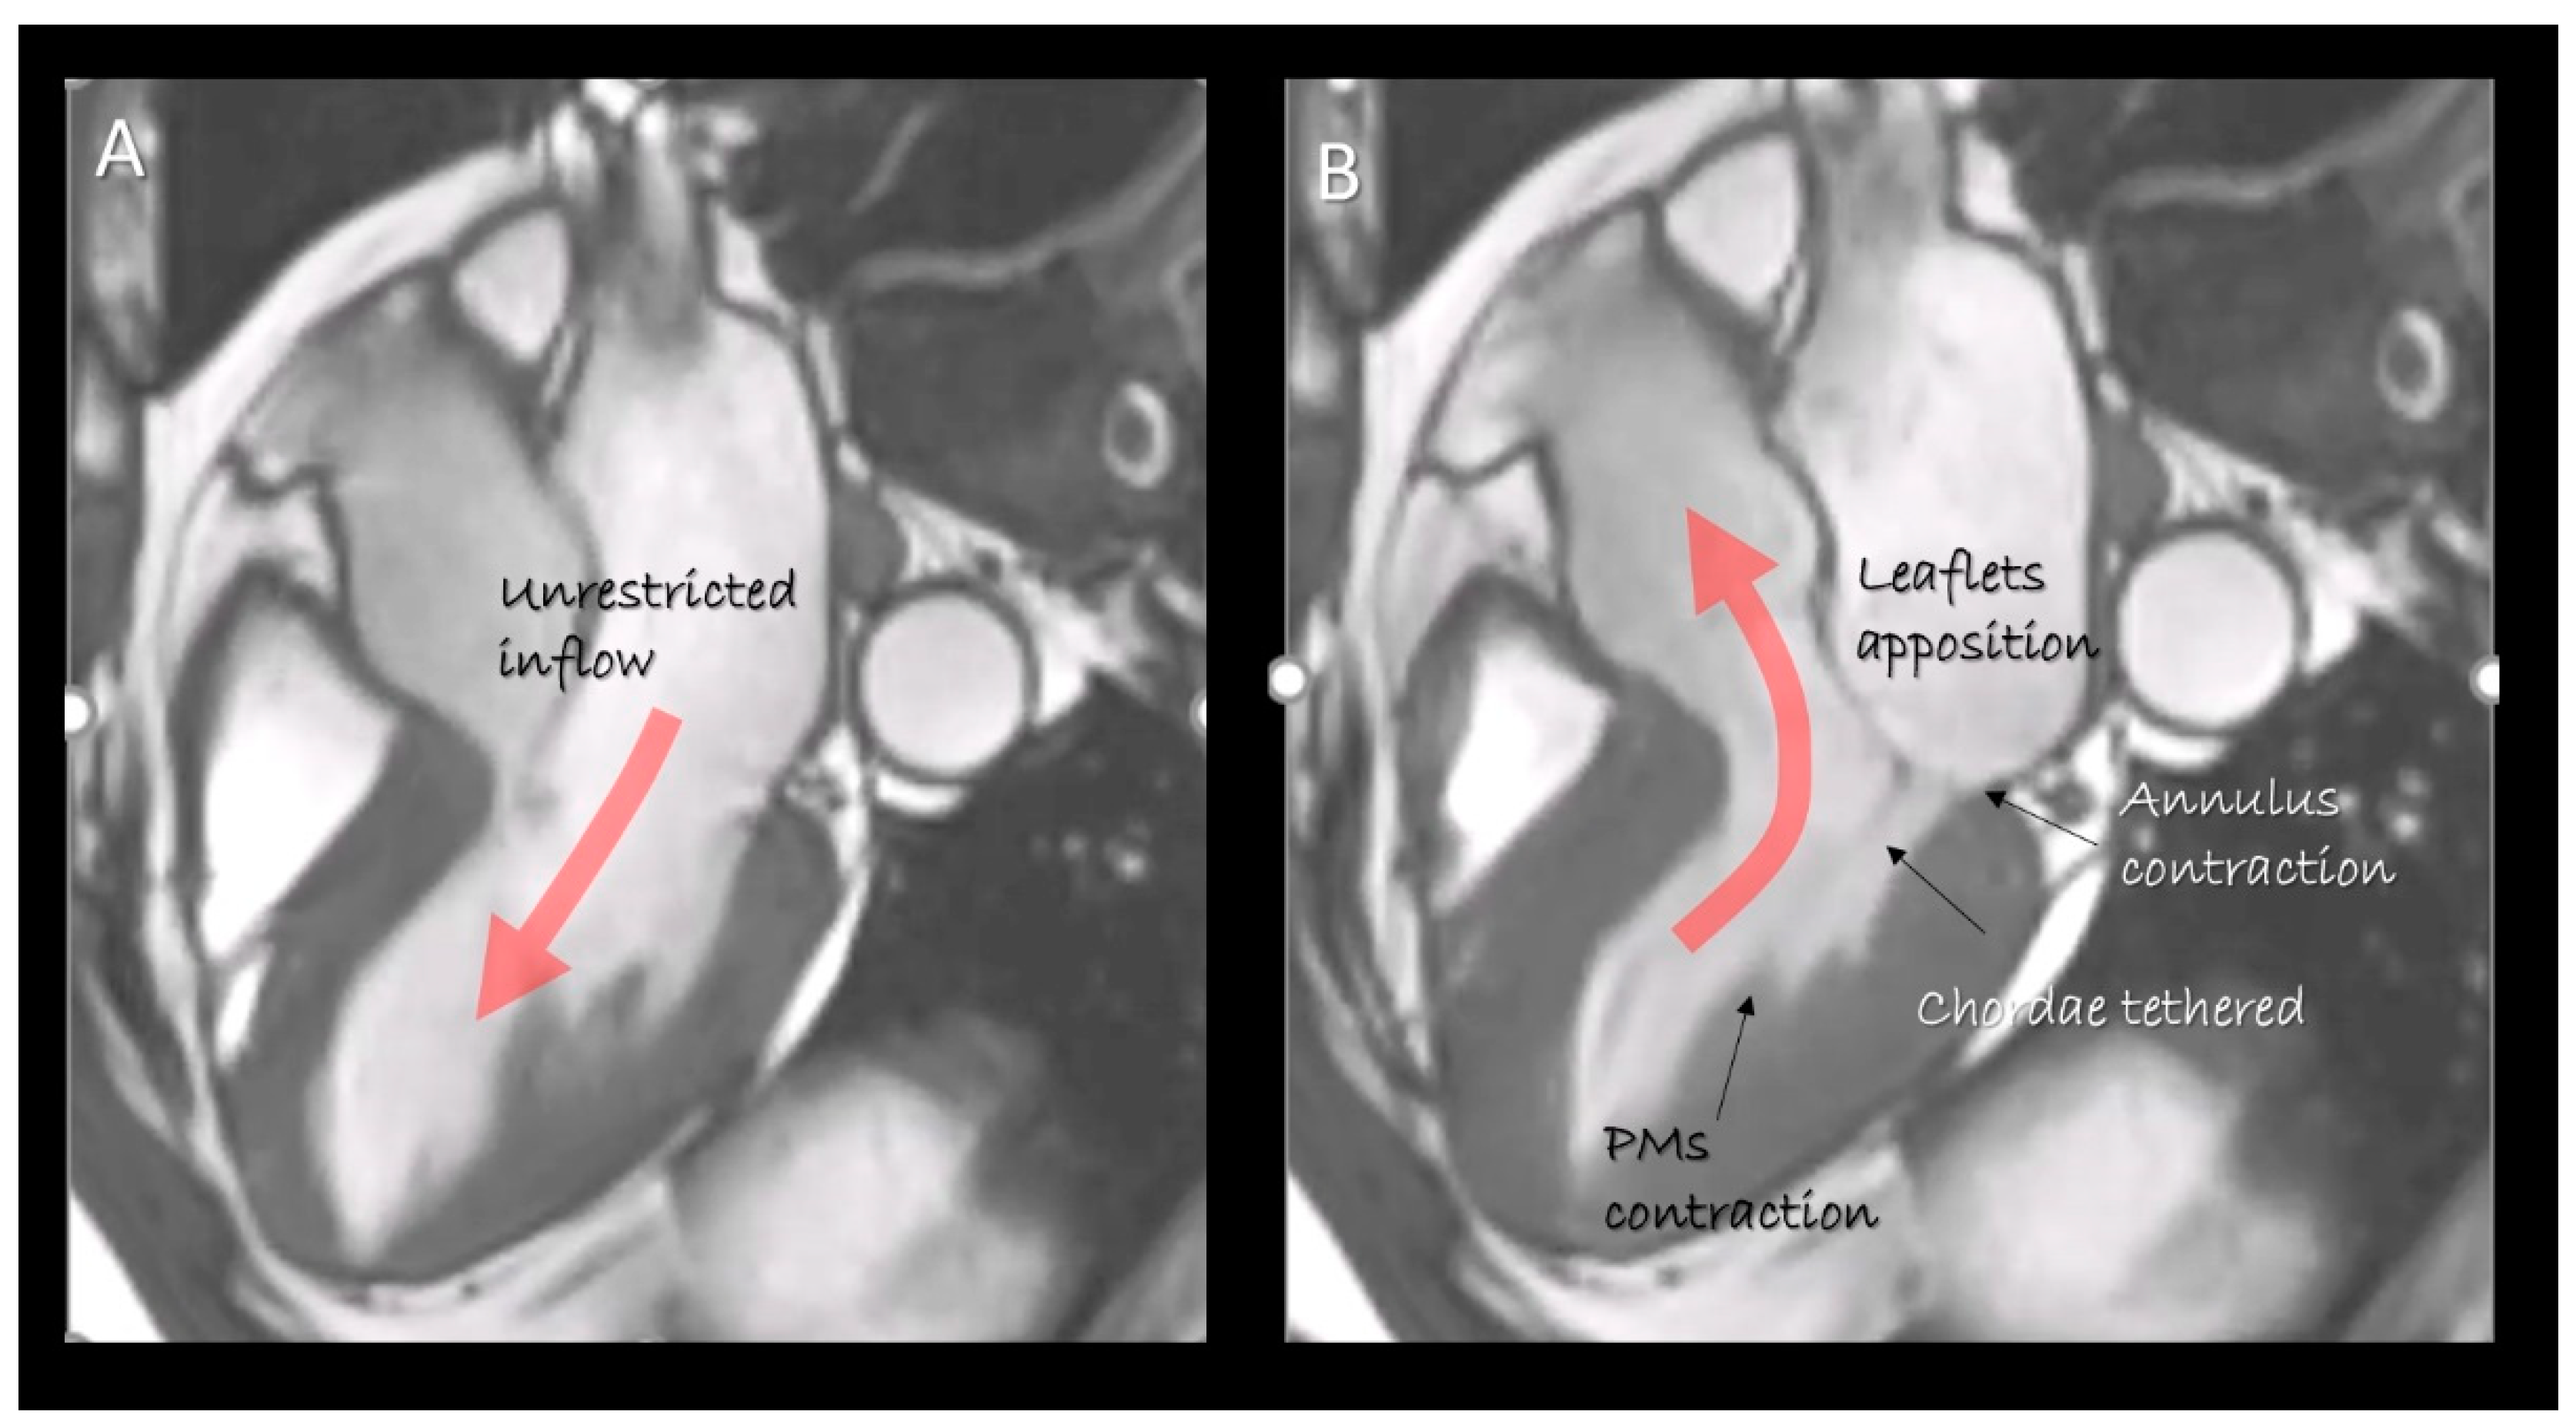

3. Mitral Leaflets

4. Chordal Apparatus

5. Papillary Muscles